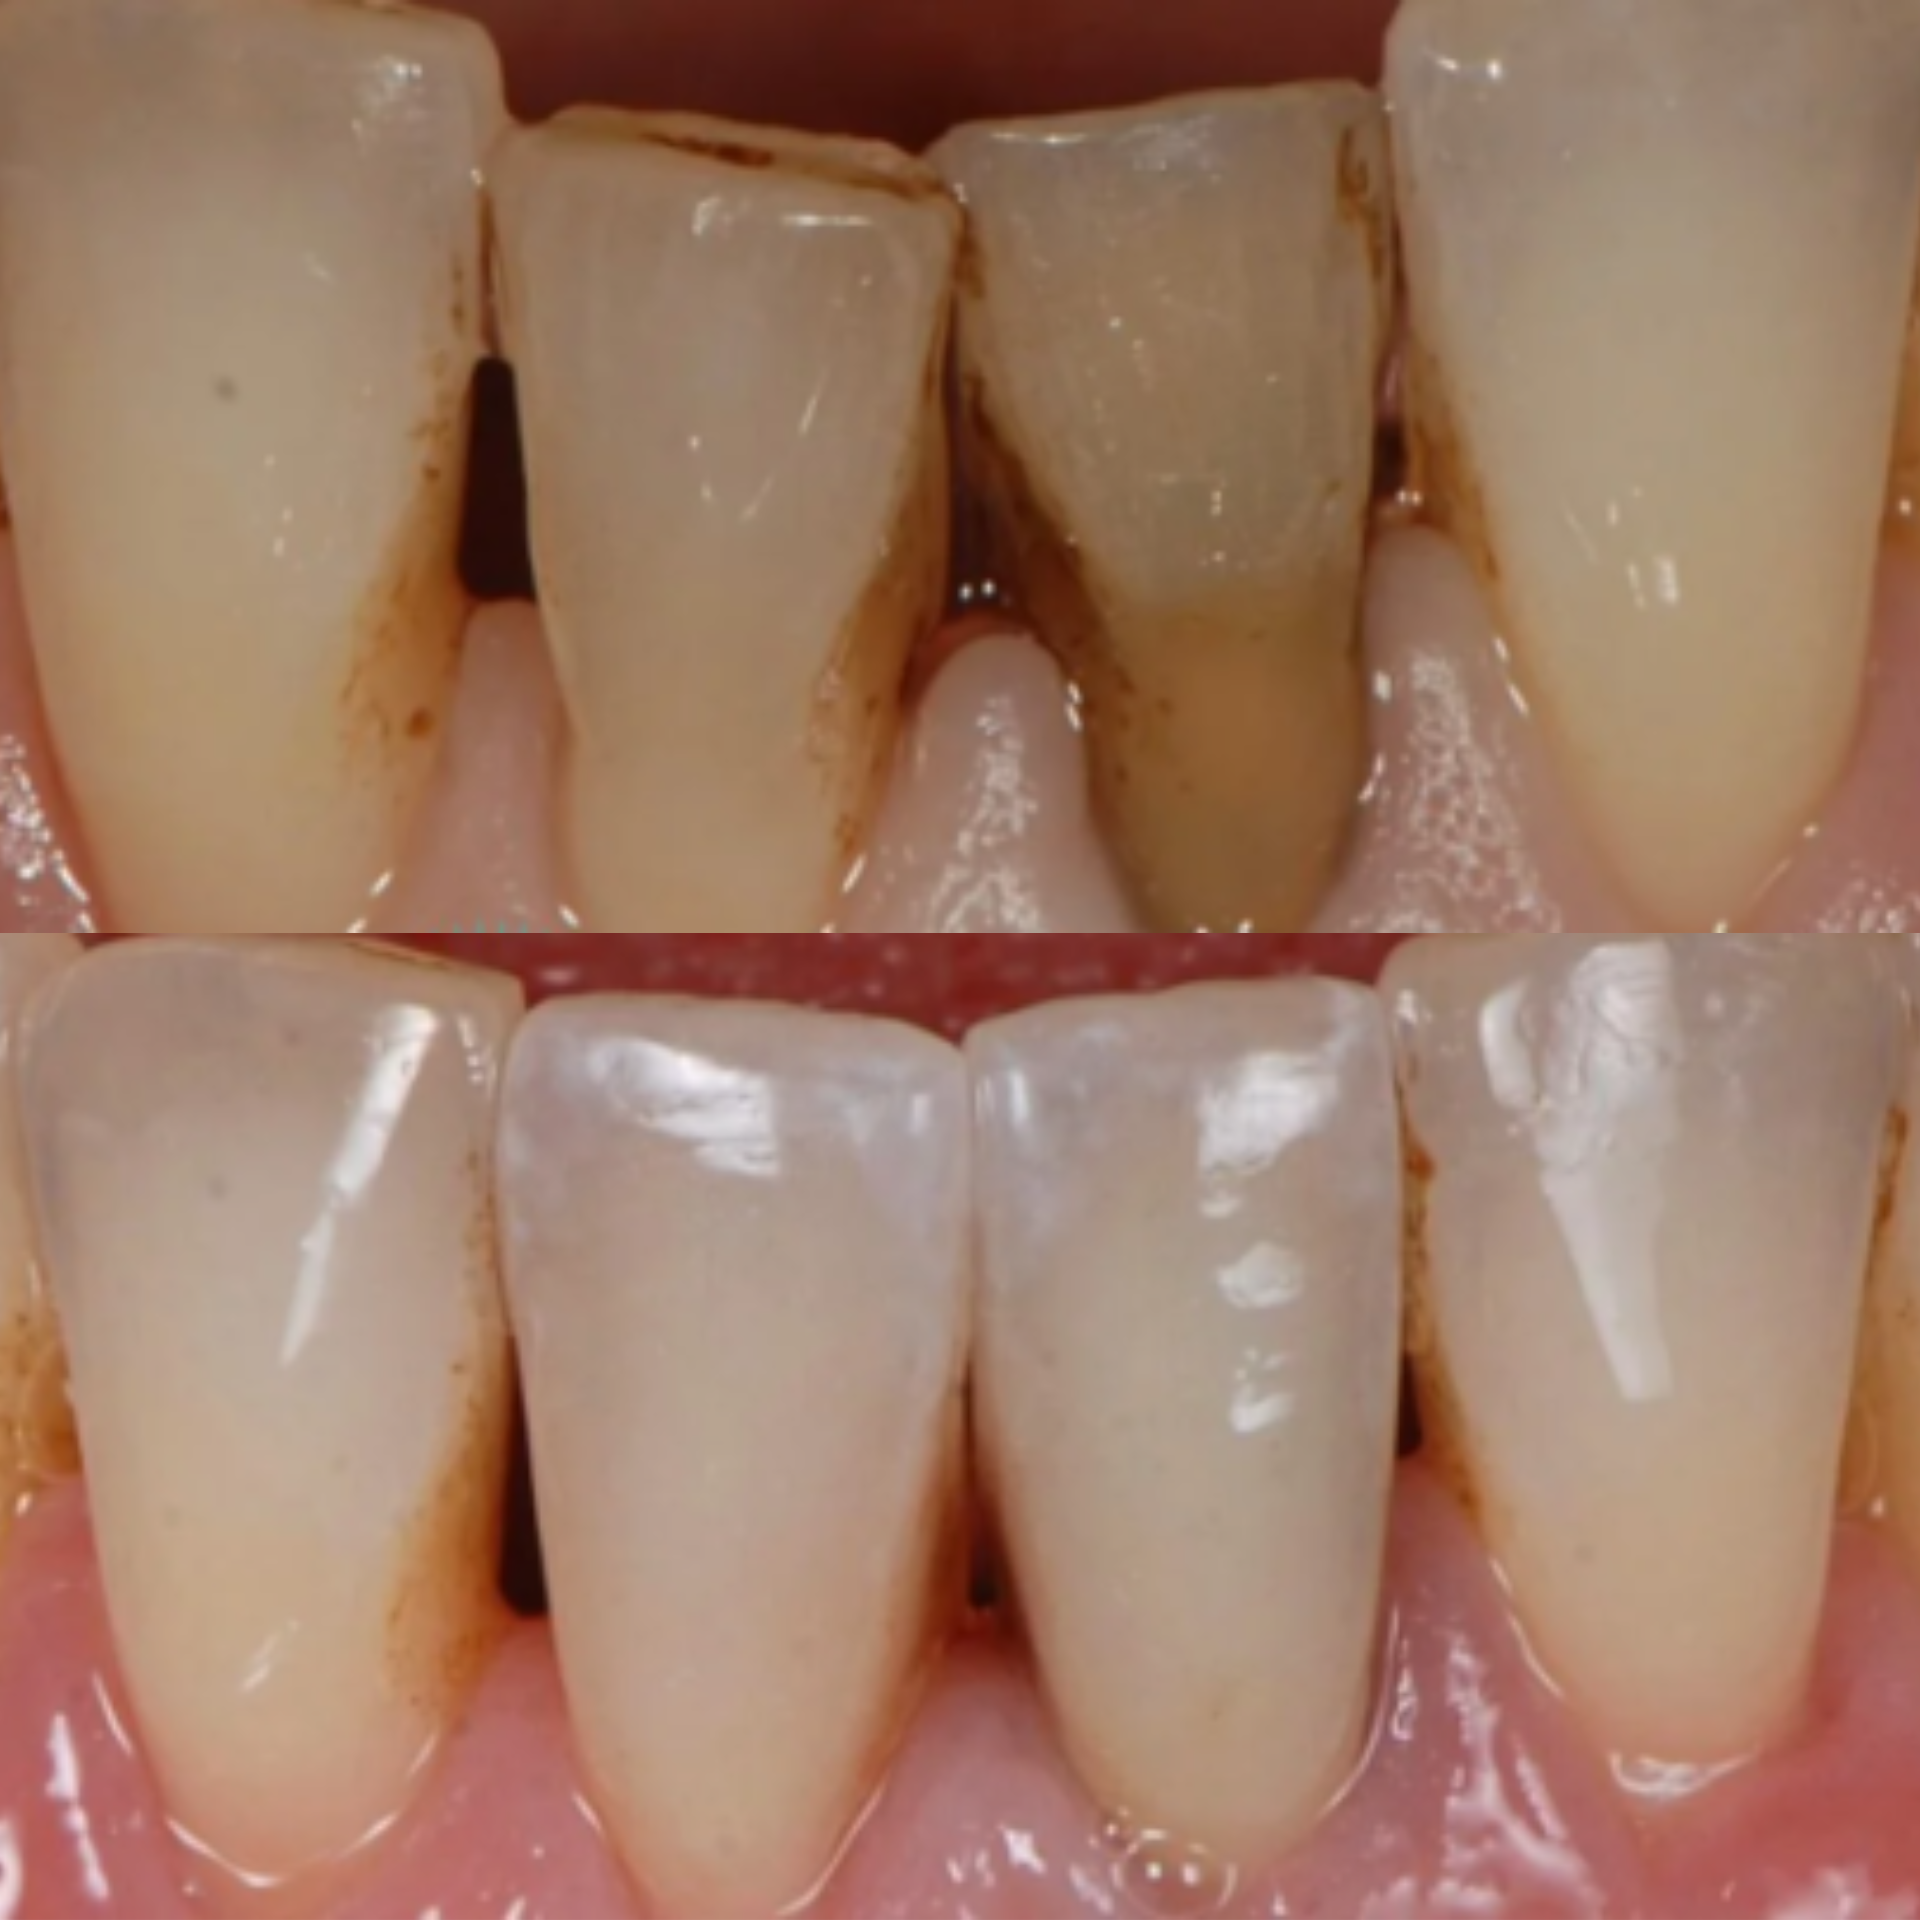

This patient presented with significant gum recession affecting the right central tooth, which ultimately required extraction.

Our team carefully planned and executed the placement of an implant supported crown to achieve a natural looking, fully functional esthetic result. The final outcome not only restored the patient’s smile, but also renewed their confidence.